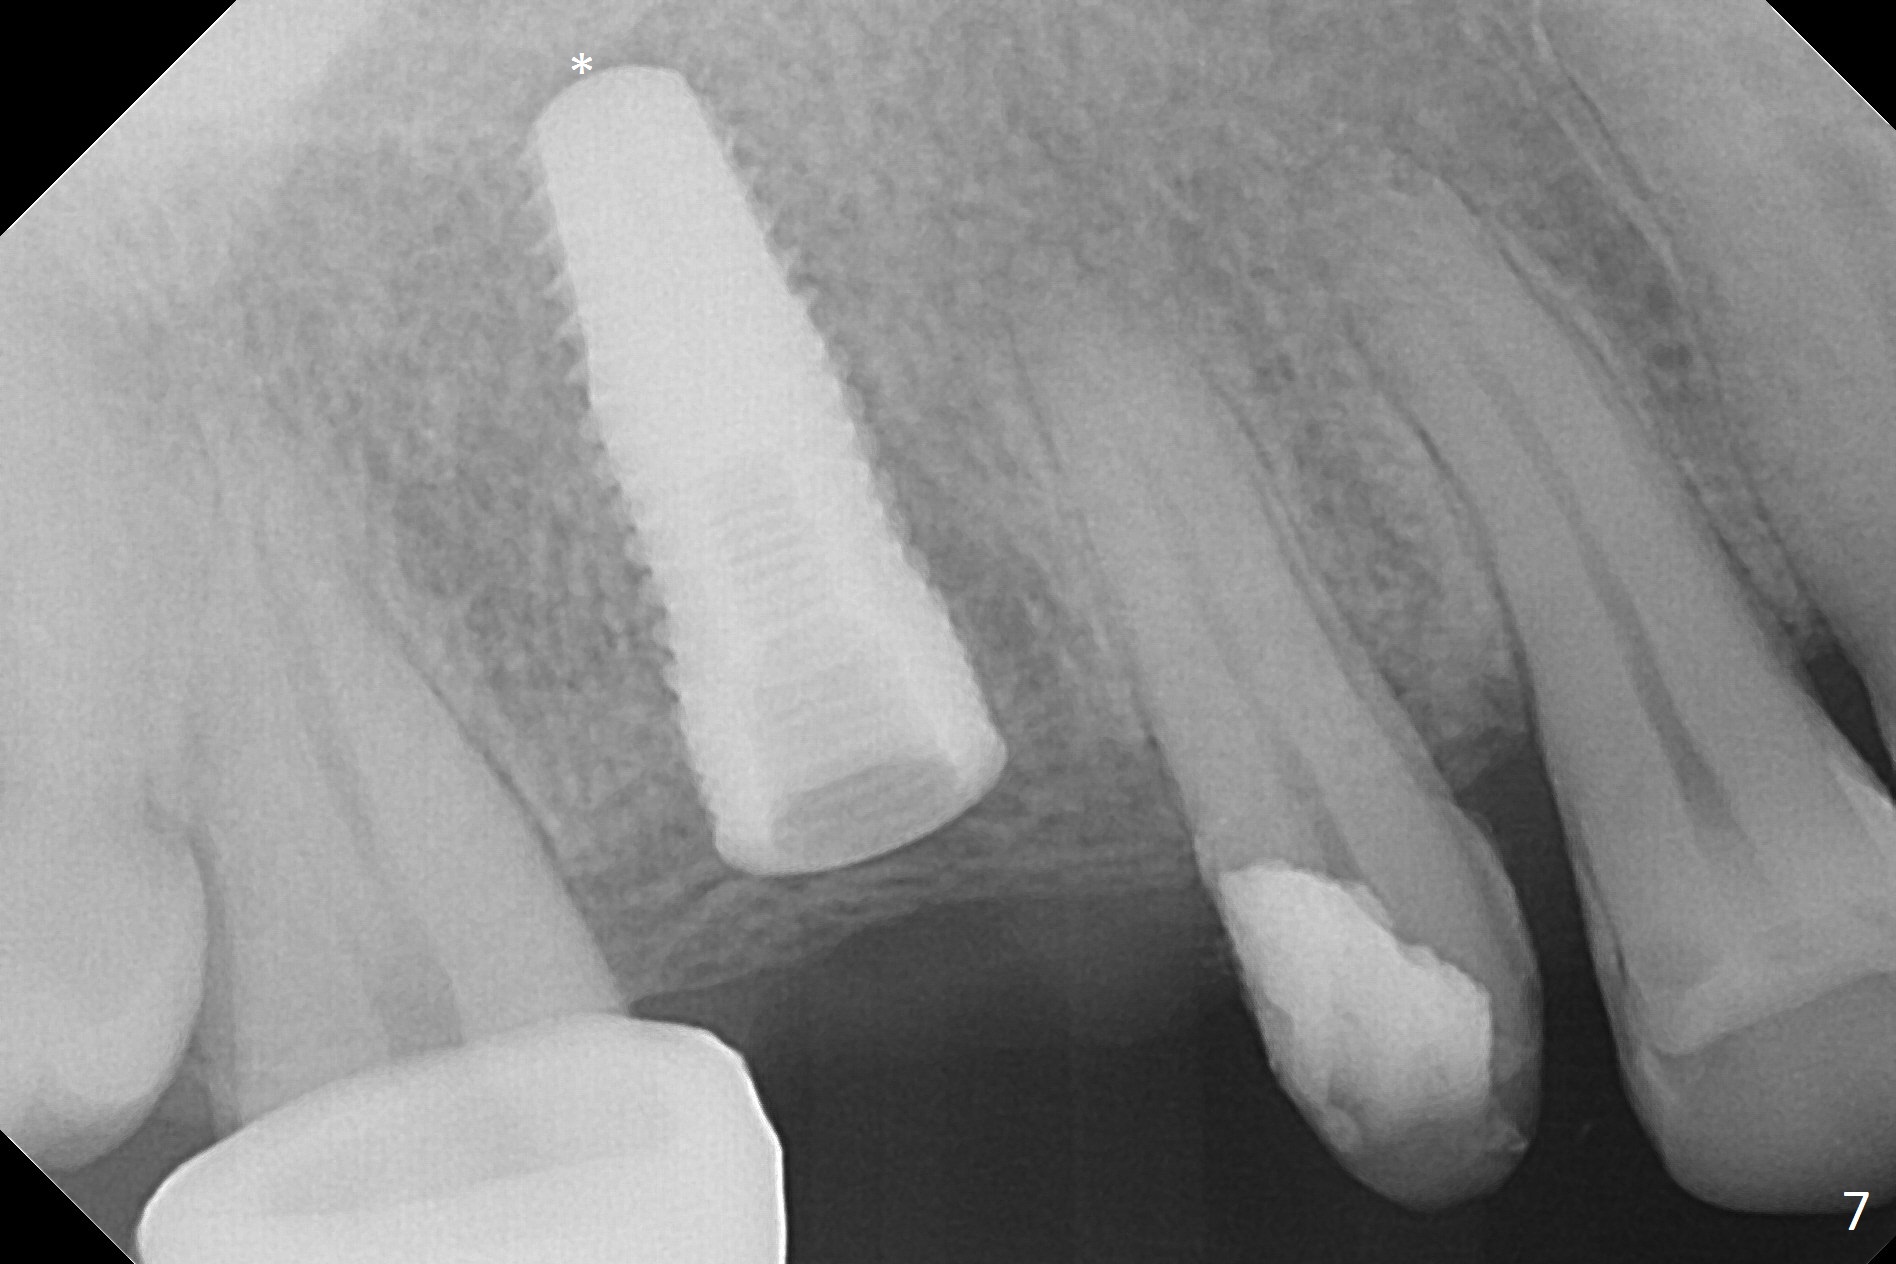

When the bridge is partially removed, the tooth #4 is found to have extensive caries. IRM is placed following carious removal (Fig.1). Magic Split testing shows that the bone density is high (flapless). Osteotomy is initiated by 1.6 mm drill, but the handle of the drill needs to shift mesial (Fig.1 red arrow). When the latter is done, the whole drill (2 mm) needs to move distal (Fig.2 double red arrows). When a 4.5x14 mm drill finishes the osteotomy, it is in the middle of the edentulous space (Fig.3). After use of 5 mm tap, a 5.3x14 mm implant cannot reach the depth (Fig.4,5). Following increase in osteotomy depth from 16 to 18 mm (gingival margin) until 5 mm drill in diameter, the implant placement level is more ideal (Fig.6,7, slightly subcrestal) with insertion torque maintaining at >55 Ncm. The sinus floor (Fig.4 arrowheads) may be penetrated when the osteotomy depth increases (Fig.7 *), but the sinus membrane remains intact.

In brief, osteotomy depth using flapless approach should be 4 mm more than the intended implant length (2 mm for gingival thickness and 2 mm for complete implant seating).